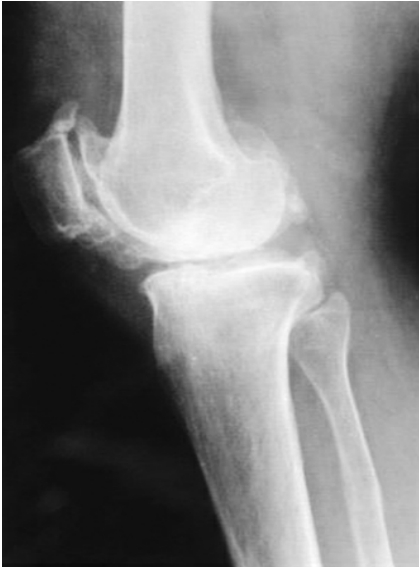

1.6.5五、膝关节骨性关节炎的诊断

1.10.7膝关节内游离体